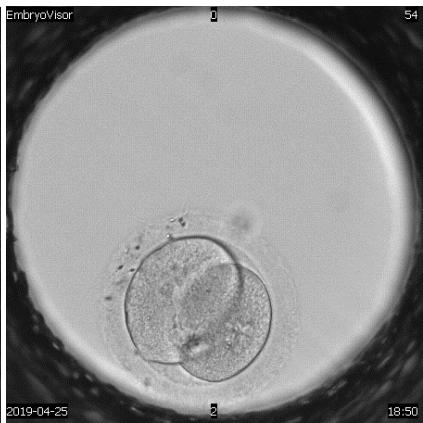

The embryological stage of ART programs is one of the most important, since the assessment of the quality of oocytes, their fertilization and in vitro cultivation to the stage of preimplantation embryos largely determines its success. Morphological evaluation of embryos is the main method of embryo selection. Time-lapse microscopy is one of the modern methods of selecting a high-quality embryo for transfer. In the analysis of many retrospective and prospective studies, they emphasize the advantage and lack of differences compared to traditional morphological assessment of the quality of embryos Almost all publications devoted to timelapse microscopy have focused on determining the timing of specific events of embryo division and then using this information to create algorithms that help to select embryo for transfer.

A detailed view of techniques used to assess human embryo development to enhance reproductive potential.